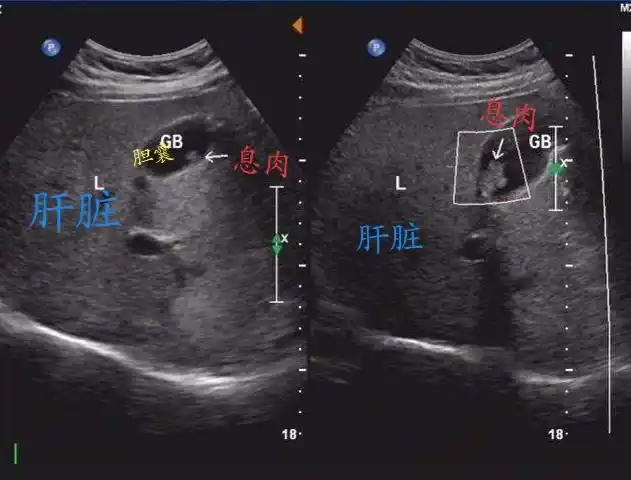

"胆囊息肉"折磨了我十年,我要"疯"了!